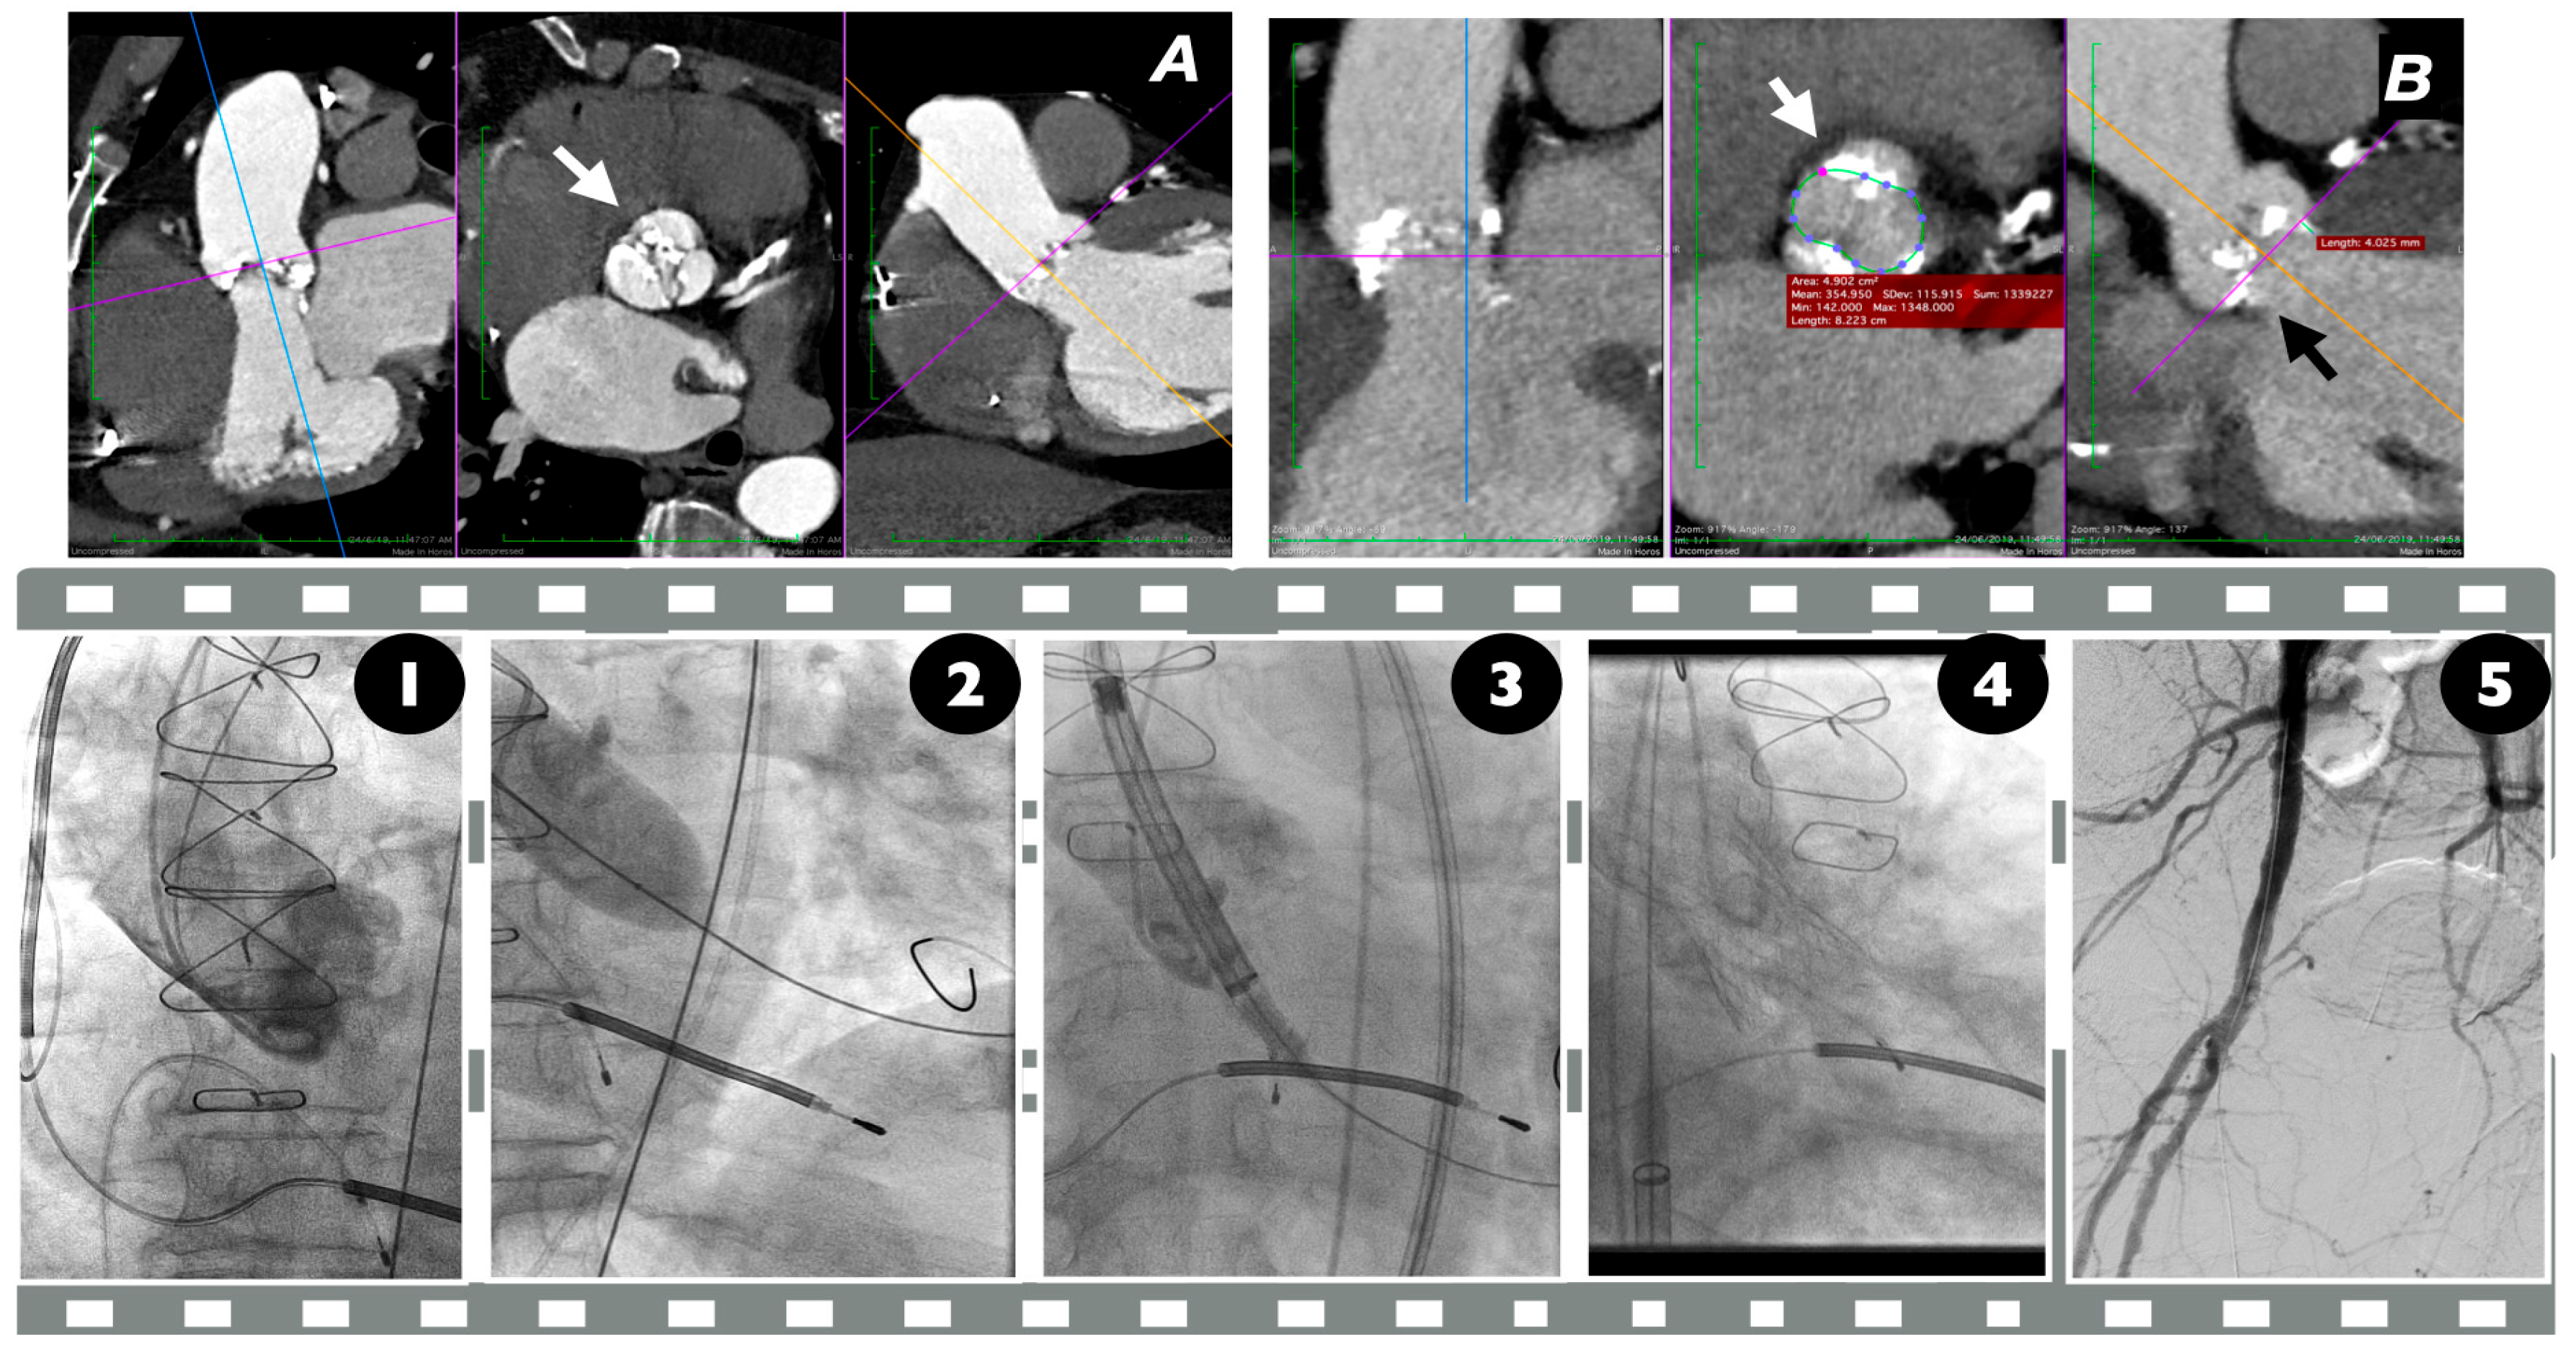

10. Implantation

12. Technical Considerations in BAV TAVI Implantation